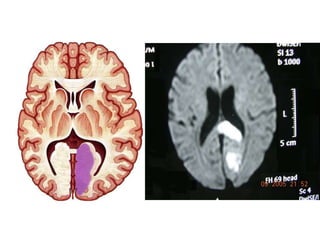

• The artery of Percheron is a rare variant of the posterior

cerebral circulation.

• The term is used to refer to a solitary arterial trunk that

branches from one of the proximal segments of either

posterior cerebral artery.

• It supplies blood to the paramedian thalami and the

rostral midbrain bilaterally.

• Percheron infarct: bilateral thalamic and mesencephalic

infarctions ; clinically, often obtunded, comatose, or

agitated, with associated hemiplegia or hemisensory loss

PERCHERON???